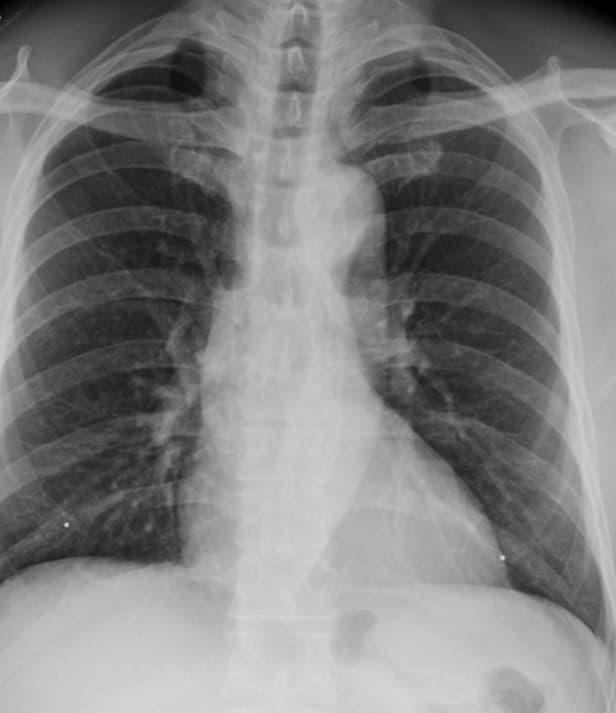

肺部 x 光片

潜伏性结核感染 (LTBI) 检测和治疗计划

东北医疗中心 的 LTBI 检测和治疗计划旨在通过检测、评估和治疗结核病感染者来消除结核病 (TB)。